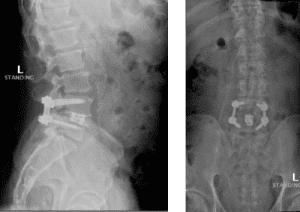

Image 3. Post-op x-rays that show L4/L5 transforaminal lumbar interbody fusion (TLIF). There was also removal the L2/L3 disc herniation but no need for instrumentation.

The herniated disc only requires decompression and removal of the herniated disc. Notice in the same flexion extension dynamic x-rays. There’s no abnormal motion at the L2/L3 level.

Dr. Imani was able to decompress both the L2/L3 level (with disc herniation removal) and the L4/L5 level. Additionally, L4/L5 level was fused using titanium screw and an expandable interbody cage. This was performed with a very small incision. The patient has no more leg pain and back pain, and is doing very well!